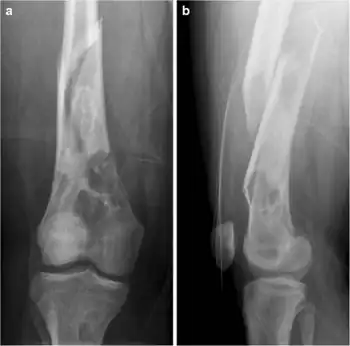

a,b)Pathological femoral fracture in Jaffe-Campanacci syndrome due to Multiple non-ossifying fibromas